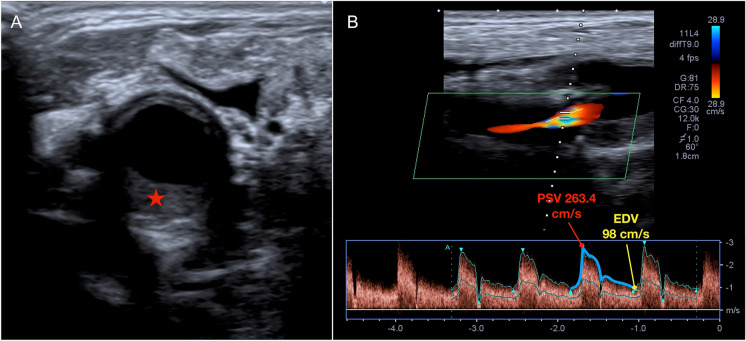

Abstract Image